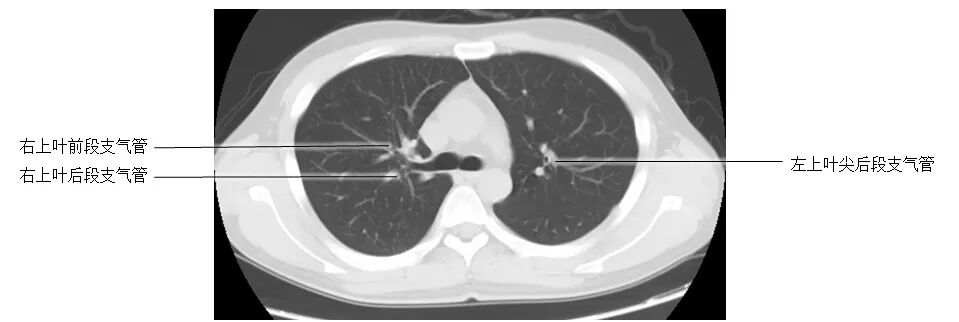

正常胸部CT影像是从横断面显示解剖和病变,可显示的结构包括胸廓、气管和支气管、肺、胸膜、纵隔和膈,CT的重建图像可从各个角度显示胸部解剖情况。不论采用何种图像显示方式,把握基本解剖结构都是必不可少的,一起学习胸部CT肺窗和纵隔窗的正常解剖。

胸部CT肺窗